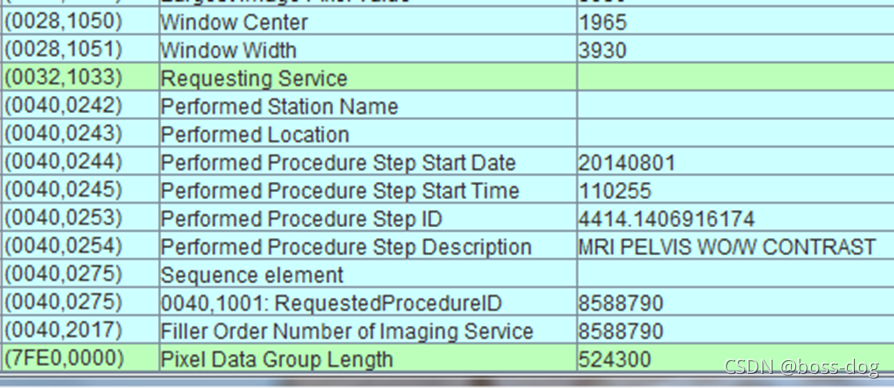

DICOM文件的格式

从影像设备里面出来的每个图片都是DICOM的格式,那么我们把文件从电脑上打开,把它拷贝或者把它打开看的话,其实它是由两部分组成,一部分是黑白图片(里面有骨头、软组织等等,显示出来人体的横截面或投影的一些信息),还有一部分是头文件(header),头文件和图像本身组合在一起。header非常重要里面包含很多的信息(如病人的信息、扫描设备的信息和扫描的时候如何进行扫描的信息)。

- 标题和图像数据存储在同一个文件中,所以重要的信息不会丢失;

- 存储了数百条关于病人、机器和数据采集的数据信息;

数据集(Data Set)和数据元素(Data Elements)

Tag(地址):譬如0020 0010地址

VR(可选项):可选字段依赖于协商的传输语法

Value Length(值长度):譬如名字给16位、字符给8位,根据值长度确定后面的Value Field(值域)

每一个信息都有一个标签(Tag),且是唯一的;

每个数据字段都有一个唯一的标记或键;

标签是是两个四位的16进制数来组成的,比如(7EF0 0010)就定义为tag标签。